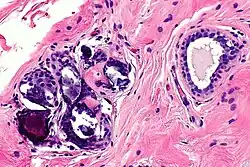

Mechanical and enzymatic (ME) methods are the most common isolation methods, although there is no standard method.[11] Accordingly, Glass and Ferretti proposed one of the ME methods which is to apply tumescent-assisted liposuction using a mechanical or ultrasound-assisted liposuction cannula. Through liposuction, the fat sample is digested by enzymatic activities of collagenase or trypsin in Dulbecco’s modified Eagle's medium (DMEM). The resultant tissue suspension undergoes incubation and agitation at around 37 °C and is filtered through a strainer to remove unnecessary debris. The cell pallet left after centrifugation is the SVF, which is seeded on the plate after the second suspension with bovine calf serum, 1% penicillin or streptomycin, and L-glutamine. The adherent properties of ADSCs on the plate allow for their isolation,[12] but due to the inconvenience of isolating the pure ADSCs, a cell-assisted lipo-transfer (CAL) is more commonly used. CAL transforms poor ADSCs into enriched ADSCs by mixing SVF isolate and aspirated fat.[13] The efficacy of CAL was proven by the increased survival rate of autologous breast augmentation when introduced around 270 ml for each breast.[14]